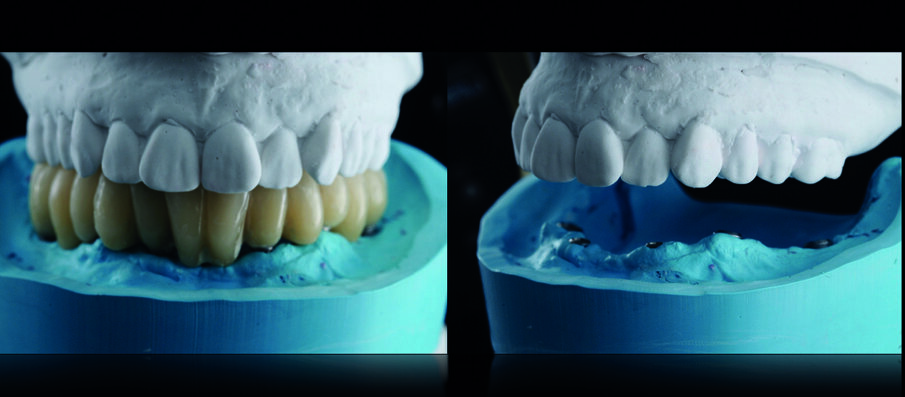

I nuovi modelli master sono stati montati in articolatore in accordo alle procedure di cross-mounting al fine di replicare dimensione verticale, rapporti sagittali tra mascella e mandibola, contatti occlusali, ingombro delle protesi e parametri estetici (Figg. 12, 13). La struttura della protesi inferiore è stata progettata al CAD ed è stata realizzata al CAM fresando un blocco in cromo-cobalto che è stata poi ceramizzata (Figg. 14-16).

La personalizzazione della protesi superiore ha previsto l’utilizzo di denti in disilicato di litio per la sua realizzazione: questo accorgimento ha permesso una durevole stabilità occlusale in assenza di usura degli elementi dentali artificiali della protesi rimovibile (Figg. 17-19).

La finalizzazione della riabilitazione ha perciò previsto due soluzioni protesiche completamente differenti tra loro: una protesi fissa inferiore avvitata su sei impianti (in metallo-ceramica) ed una protesi rimovibile superiore con denti personalizzati in ceramica presso-fusa) (Figg. 20, 21).